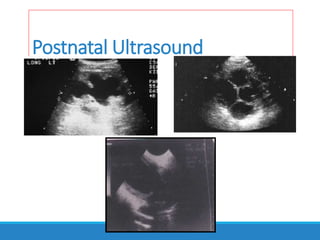

Postnatal Ultrasound

To evaluate the effect of PUV on the urinary tract rather than to

diagnose PUV.

Typical finding: wide prostatic urethra,thick-walled bladder and upper

tract dilatation.

Assessment of renal parenchyma.